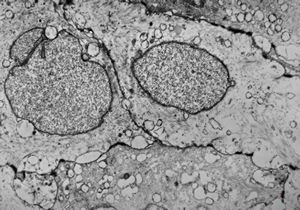

F,50y. | progressive multifocal leukoencephalopathy- viral particles in a glial cell